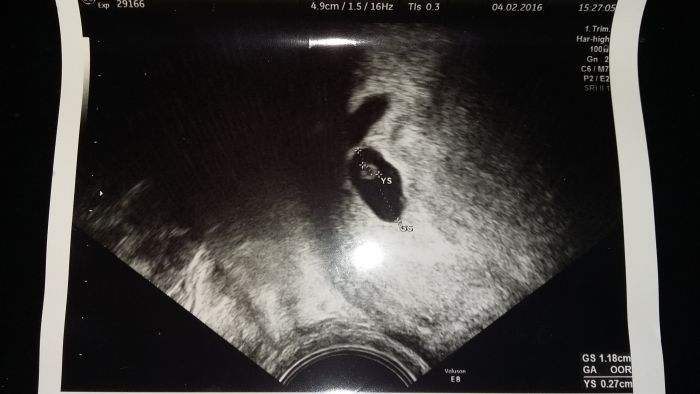

Přikládám fotku ze včerejšího utz. Jsou tam i "rozmery" (smarja, to je jak u skříně :-))) )a je to hodně malý, že? Nemohla byste mi nektera "poradit " ,v kolikatym tt zhruba muzu byt,Prosím?

GS 11,8 mm YS 2,7 mm

Anamor hezká fotka. Je opravdu ještě malinký. Myslím si, že by to mohl být tak pátý týden...

[849000] :-) jde tam vidět i to mizející dvojče... možná proto to je takový pidi ;-)

[848996] YS je velikost embrya? No já koukám na svůj první utz a v 8 tt měl prcek 1 cm.  Chodím na ko každý dva týdny a vyroste vždycky o 2 cm.  A kdys měla poslední ms?  Je těžký nestresovat se viď.

[849002] YS je zloutkovy vacek. Poslední MS 7.12. A stres je na každodenním pořádku.